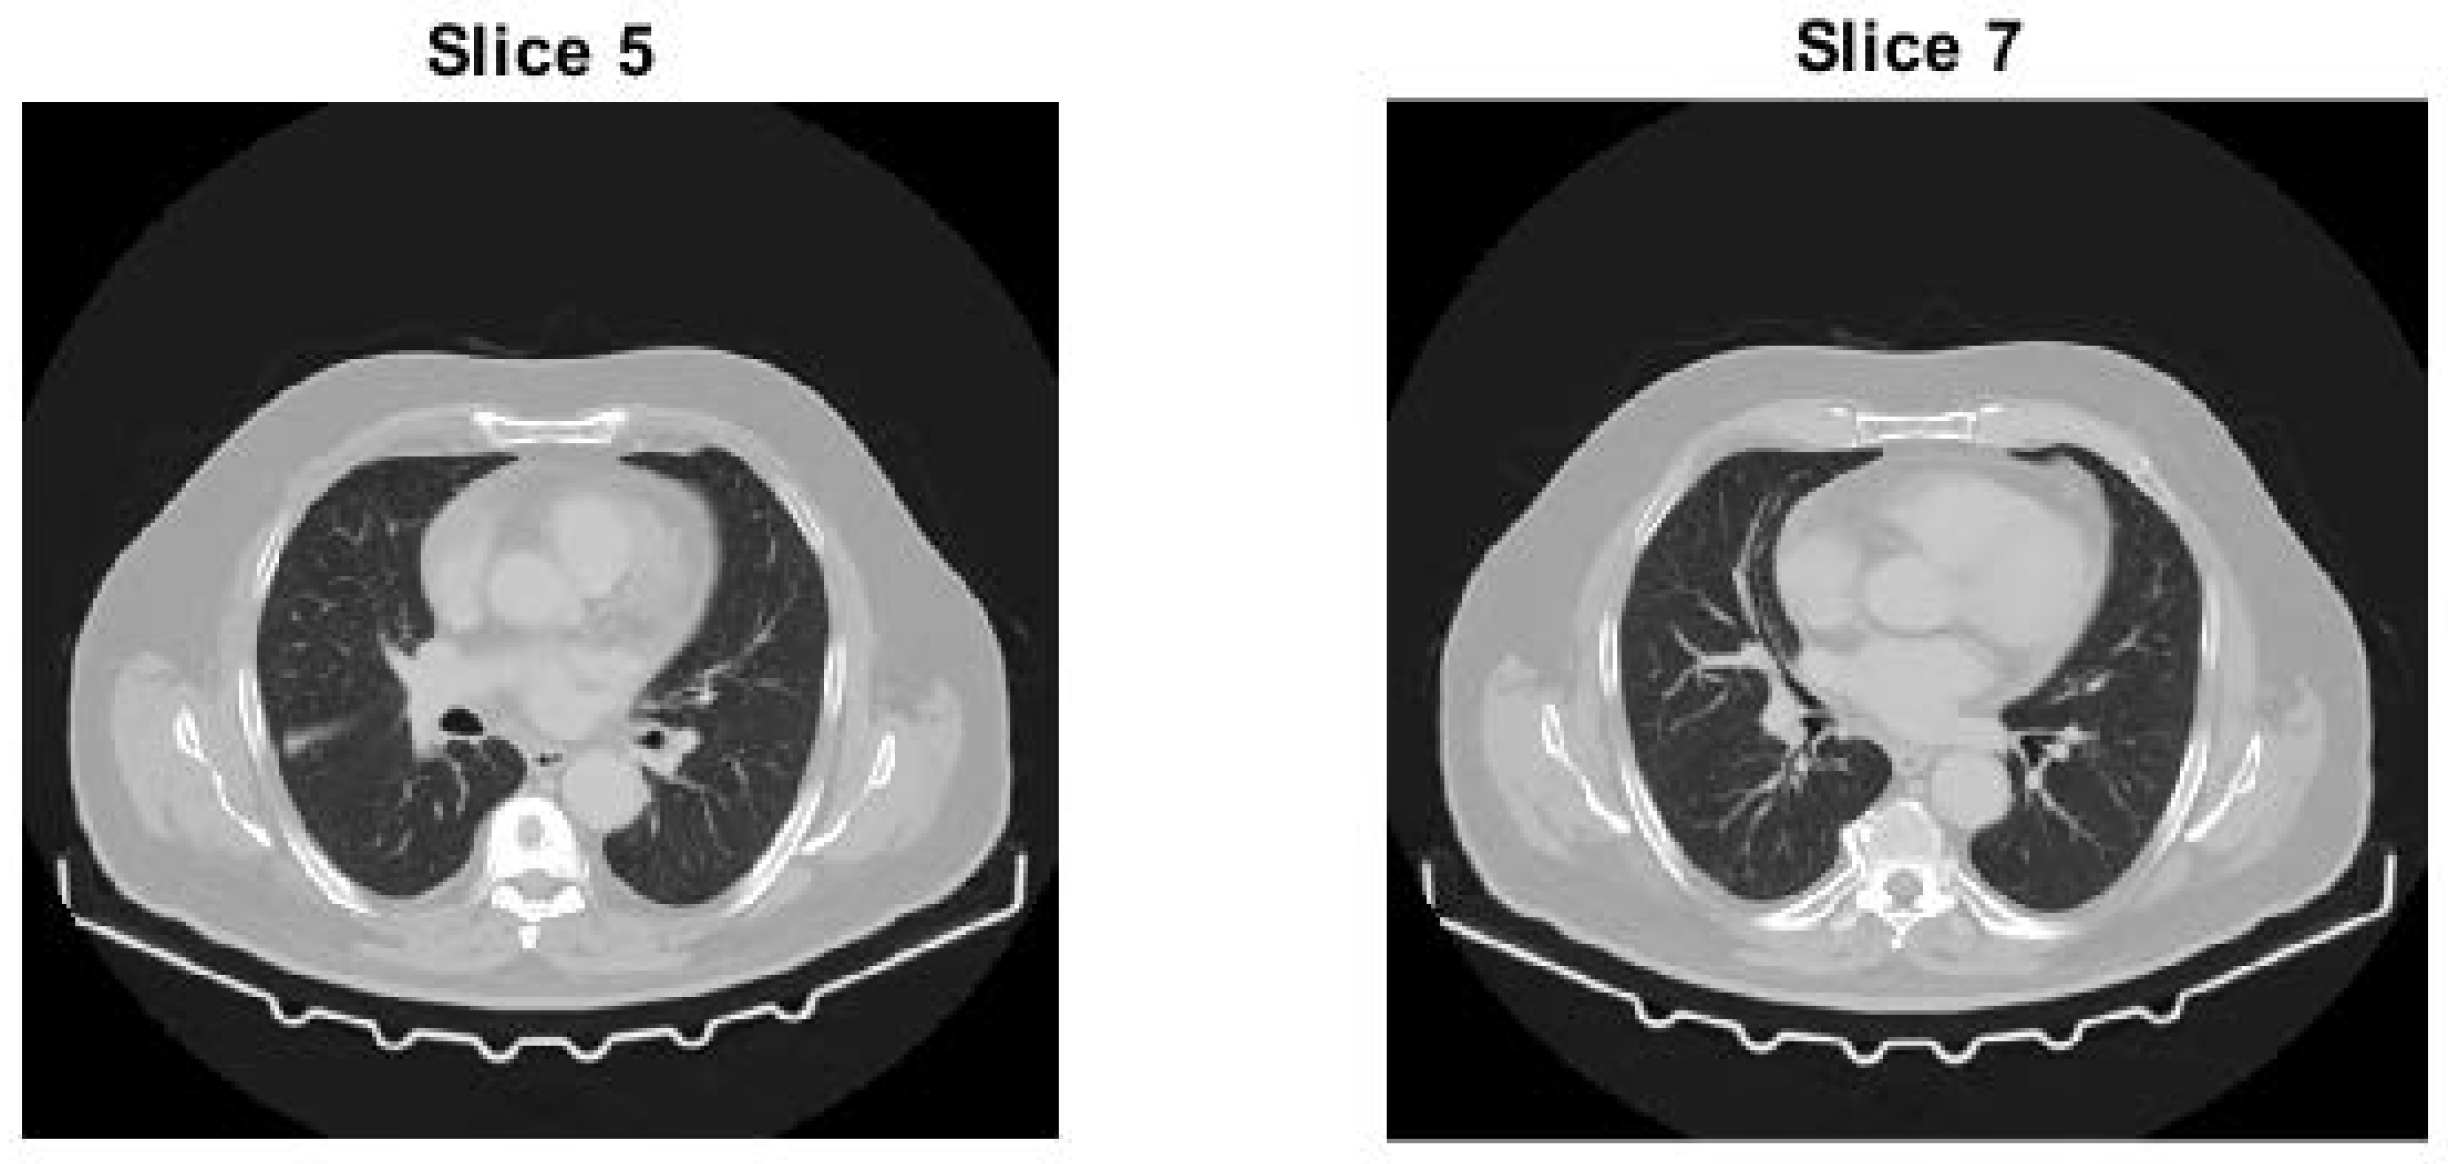

- Test image 3 is a 3D sub-volume extracted from a high-resolution CT scan of a human body, stored in DICOM format as a 16-bit unsigned integer (uint16) volumetric dataset.

4.3.3. Test Slice of Test Image 3